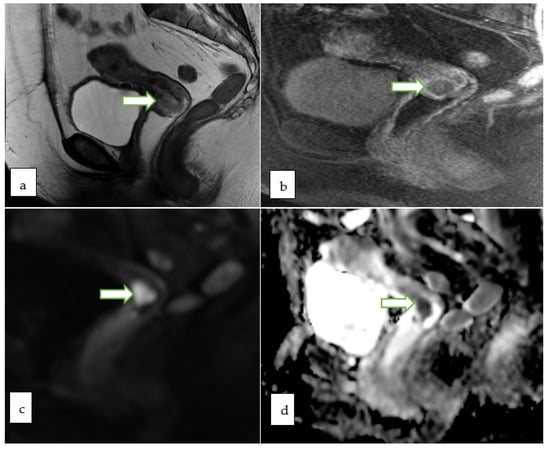

- MRI is regarded as the gold standard for local delineation of most gynecological malignancies owing to superb soft tissue contrast and resolution without exposing the patients to ionizing radiations. In addition, DCE and DWI provide additional data regarding tissue perfusion and cellular density, respectively.